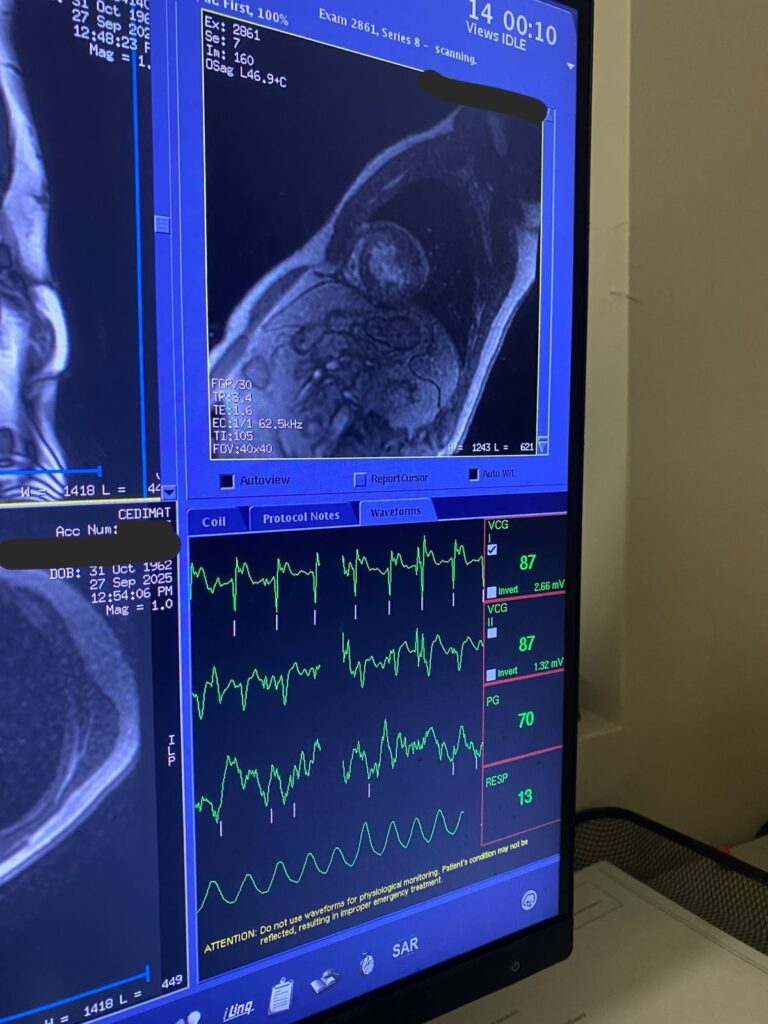

Santo Domingo. – Los Centros de Diagnóstico y Medicina Avanzada y de Conferencias Médicas y Telemedicina (CEDIMAT), marcó un nuevo hito en la medicina cardiovascular del país al realizar con éxito la primera resonancia magnética cardíaca de estrés, una tecnología avanzada que permite evaluar con precisión la función del corazón bajo condiciones simuladas de esfuerzo físico.

La Resonancia Cardiaca de Estrés o de esfuerzo, se realiza con un medicamento llamado Regadenoson, perteneciente al grupo de fármacos vasodilatadores, permite detectar isquemia o infarto al músculo cardíaco causado por una obstrucción en arterias coronarias.

A diferencia de otras pruebas de esfuerzo, la resonancia magnética de estrés no utiliza radiación ionizante y ofrece una visión tridimensional de la anatomía y función del corazón, lo que la convierte en una opción altamente confiable y segura para los pacientes.

Este procedimiento fue llevado a cabo por el equipo de Imágenes Cardíacas de CEDIMAT bajo la coordinación de la Dra. Pamela Piña, cardióloga e imagenóloga cardiovascular con el Board Norteamericano de Resonancia Magnética Cardíaca. Utilizando tecnología de punta y protocolos internacionales que garantizan la seguridad y eficacia del estudio, la resonancia de estrés representa un avance significativo en el diagnóstico de enfermedades cardíacas, especialmente en casos donde otros métodos tradicionales, como las pruebas de esfuerzo convencionales, el ecocardiograma de estrés o la tomografía coronaria ofrecen resultados no concluyentes.

“Con esta nueva herramienta diagnóstica podemos obtener imágenes detalladas del corazón en movimiento, identificar áreas con falta de irrigación sanguínea y evaluar la viabilidad del tejido cardíaco, todo sin necesidad de procedimientos invasivos”, explicó la Dra. Pamela Piña.